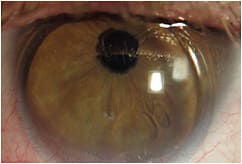

A 54-year-old monocular patient who had aphakia OS reported with corneal GP lens fit issues. His current contact lens was inferiorly decentered and was binding to his cornea without movement (Figures 2 and 3).